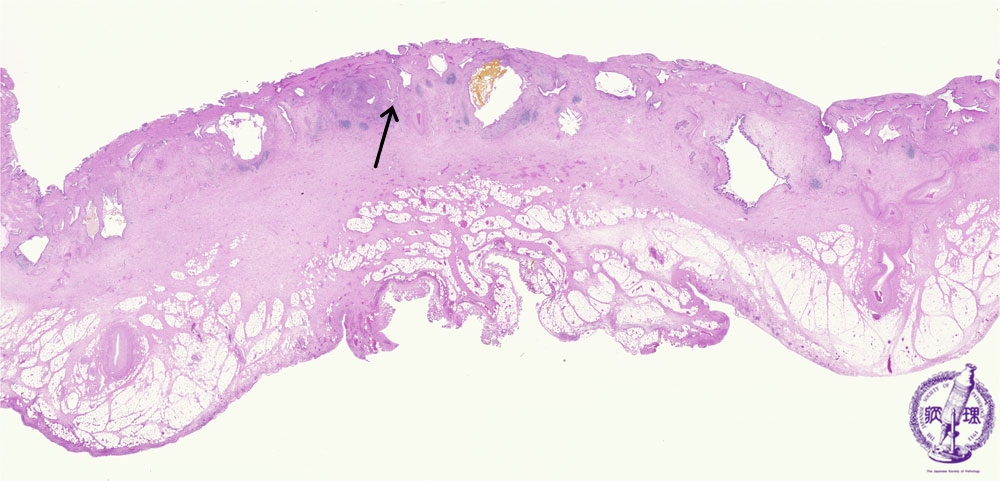

Microscopic image(HE stain, loupe view):The gallbladder is markedly thickened with fibrosis which involves the mucosal, muscular, and subserosal layers. Many epithelial lined cyst-like invaginations form sinus tracts which penetrate the muscularis into the subserosa (Rokitansky-Aschoff sinuses). At the center, bile congestion (tan) is observed in a Rokitansky-Aschoff sinus.